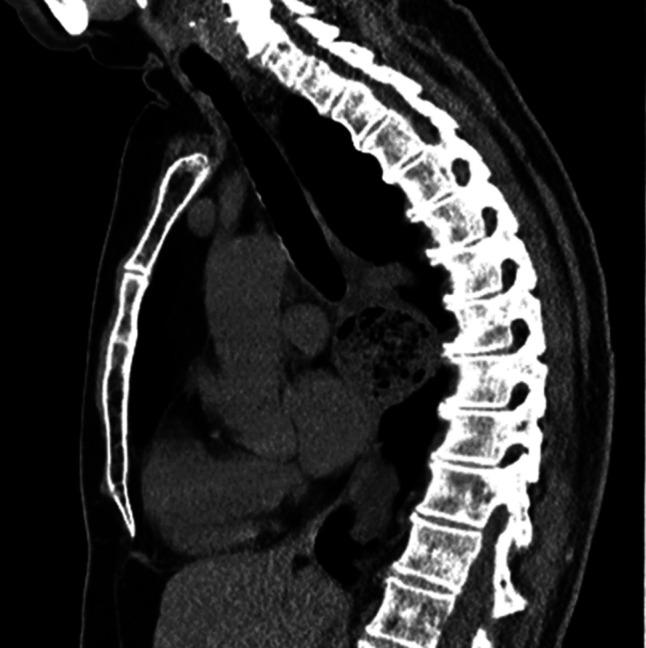

Esophageal diverticulum (ED) is a rare condition with a clinical presentation that can be variable. Esophageal diverticulum has been associated with motility disorders; however, the association with mid-ED is less clear. Hypercontractile esophagus, also known as jackhammer esophagus, is a rare motility disorder of peristalsis diagnosed by esophageal high-resolution manometry after exclusion of mechanical obstruction. We describe the second reported case of mid-ED secondary to hypercontractile esophagus successfully treated through robotic diverticulectomy with long myotomy. KEYWORDS: esophagus; esophageal manometry; motility; diverticular disease.

食管憩室(ED)是一种罕见疾病,临床表现多变。食管憩室与动力障碍有关;然而,与中段食管憩室的关联尚不清楚。高收缩性食管,也称为风钻食管,是一种罕见的蠕动动力障碍,在排除机械性梗阻后通过食管高分辨率测压诊断。我们描述了第二例因高收缩性食管继发中段食管憩室的病例,该病例通过机器人憩室切除术加延长肌切开术成功治疗。关键词:食管;食管测压;动力;憩室病